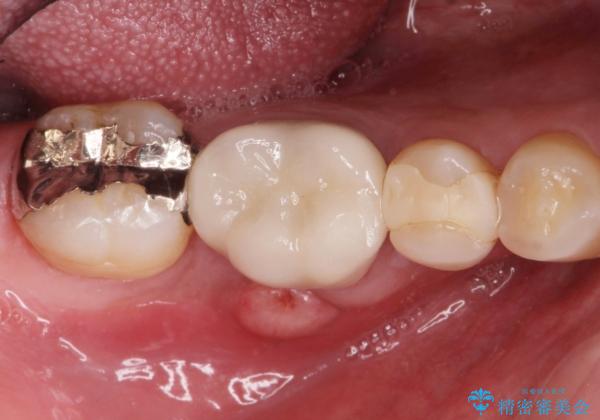

歯茎が腫れた。ジルコニアクラウンやりかえ。

- メンテナンスで来院された患者様です。

歯茎が腫れたとの事で歯の神経が失活していたので精密根管治療を行い、ジルコニアクラウンで治療を行いました。

神経が失活しているので痛みは感じにくいですがこのまま放置をしてしまうと骨が溶けたり痛みが出たりします。

このように歯茎にニキビみたいな物が出た場合、あるいは存在する場合すぐに歯科医院に相談することをおすすめします。